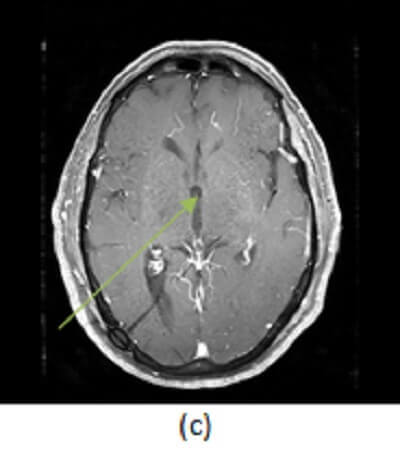

Figure 1: circumscribed FLAIR hyperintense mass at the foramen of Monroe (a, red arrow) is iso to slightly hyperintense to CSF on T1 sequences (b, blue arrow) and does not enhance on post contrast T1 imaging (c, green arrow) .

Colloid cyst is a benign congenital cystic mass that originates from the foregut like other brain cysts (neurenteric and Rathke’s cleft). The mass is typically hyperdense on CT, variable signal on T1 and T2 depending on its water /cholesterol content, nonenhancing and centered in the foramen of Monroe. Although benign, colloid cysts can cause sudden ventricular obstruction leading to rapid onset hydrocephalus and transtentorial herniation resulting in sudden death. Approximately 50% are asymptomatic. Headache is the most common presenting symptom.